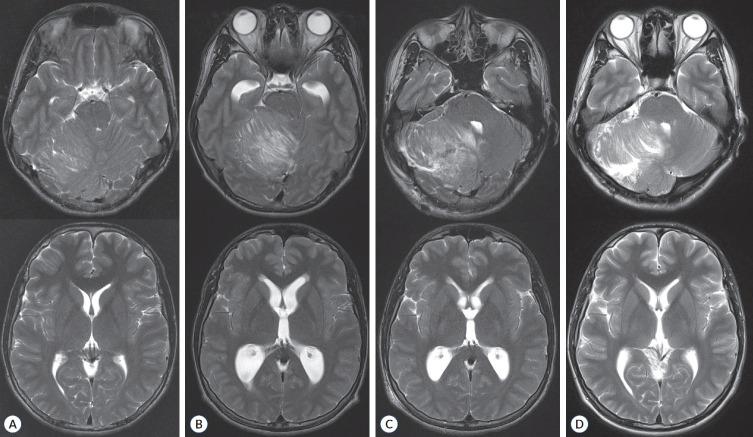

Pathogenic germline variants (PGVs) are increasingly recognized as critical elements in pediatric cancer predisposition. Determining the pathogenicity of germline variants is a dynamic process, with advancements in next-generation sequencing and expanding genome databases reshaping our understanding of cancer genomics. This article reviews the role of PGVs in key oncogenic pathways, including RTK (receptor tyrosine kinase)/RAS/MAPK (mitogen-activated protein kinase), PI3K (phosphatidylinositol 3-kinase)/AKT (v-akt murine thymoma viral oncogene homolog 1), WNT (wingless-type), and Hedgehog signaling, highlighting their associations with specific cancer predisposition syndromes and neurosurgical implications. Most PGVs are inherited in an autosomal dominant pattern and are frequent in tumor suppressor genes, while autosomal recessive conditions like Ataxia-telangiectasia and Fanconi anemia are less common. Germline variants in proto-oncogenes such as PTPN11, KRAS, and HRAS are associated with RASopathies, including Noonan and Costello syndromes, which show variable cancer risks. Similarly, PTEN PGVs, linked to Cowden syndrome, and DICER1 PGVs, responsible for DICER1 syndrome, exemplify the diverse clinical presentations and risks of pediatric cancer predisposition syndromes. Medulloblastoma, a pediatric-specific brain tumor, shows an increasing proportion of PGVs, with approximately 12% of all medulloblastomas harboring PGVs in APC, PTCH1, SUFU, and ELP1 in the WNT-activated and sonic hedgehog-activated subtypes. Emerging evidence suggests that approximately 8.5-20% of pediatric cancer patients harbor PGVs, with a substantial proportion arising de novo. Routine germline screening for pediatric cancer patients is increasingly recommended, as many PGVs lack family history. Programs like STREAM (Solid Tumor REsearch And Magic) in Korea underscore the importance of comprehensive pediatric genome databases for personalized precision medicine. As neurosurgeons are frequently the first to encounter central nervous system tumor manifestations, a robust understanding of genomic medicine is essential. This review emphasizes the need for international collaboration to develop actionable insights into pediatric cancer genomics, ultimately improving diagnostic, therapeutic, and preventive strategies.

致病性种系变异(PGVs)日益被认为是儿童癌症易感性的关键因素。确定种系变异的致病性是一个动态过程,随着下一代测序技术的进步和基因组数据库的不断扩展,我们对癌症基因组学的理解也在不断重塑。本文综述了PGVs在关键致癌途径中的作用,包括RTK(受体酪氨酸激酶)/RAS/MAPK(丝裂原活化蛋白激酶)、PI3K(磷脂酰肌醇3激酶)/AKT(v-akt小鼠胸腺瘤病毒癌基因同源物1)、WNT(无翅型)和Hedgehog信号通路,强调了它们与特定癌症易感性综合征的关联以及神经外科意义。大多数PGVs以常染色体显性模式遗传,在肿瘤抑制基因中较为常见,而像共济失调毛细血管扩张症和范可尼贫血等常染色体隐性疾病则较少见。原癌基因中的种系变异,如PTPN11、KRAS和HRAS,与RASopathies相关,包括努南综合征和科斯特洛综合征,这些综合征表现出不同的癌症风险。同样,与考登综合征相关的PTEN PGVs和导致DICER1综合征的DICER1 PGVs,体现了儿童癌症易感性综合征的多样临床表现和风险。髓母细胞瘤是一种儿童特有的脑肿瘤,PGVs的比例越来越高,在WNT激活型和音猬因子激活型亚型的所有髓母细胞瘤中,约12%在APC、PTCH1、SUFU和ELP1中存在PGVs。新出现的证据表明,约8.5%-20%的儿童癌症患者携带PGVs,其中很大一部分是新发的。由于许多PGVs缺乏家族史,越来越多的人建议对儿童癌症患者进行常规种系筛查。韩国的STREAM(实体瘤研究与魔法)等项目强调了全面的儿童基因组数据库对个性化精准医学的重要性。由于神经外科医生常常是首先遇到中枢神经系统肿瘤表现的人,因此对基因组医学有深入的了解至关重要。本综述强调了开展国际合作以深入了解儿童癌症基因组学从而最终改善诊断、治疗和预防策略的必要性。